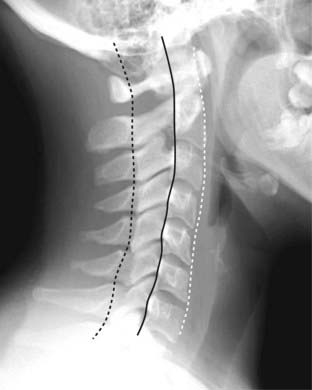

Figure 24-2 The three cervical lines.

The lateral view of the cervical spine enables a quick assessment for spinal fracture/subluxation before further studies are performed that might involve motion of the patient’s neck. Three parallel arcuate lines should smoothly join all of the spinolaminar white lines, which are the junctions between the laminae and the spinous processes (dotted black line), a second line should join all of the posterior aspects of the vertebral bodies (solid black line), and a third should join all of the anterior aspects of the vertebral bodies (dotted white line).

imageIn the cervical spine, three parallel arcuate lines should smoothly join (1) all of the spinolaminar white lines (the junction between the lamina and the spinous process), (2) the posterior aspects of the vertebral bodies, and (3) all of the anterior aspects of the vertebral bodies. Alterations in the smooth curvature of these three lines may indicate forward or backward displacement of all or part of the vertebral body (Fig. 24-2).

imageAt the beginning of this chapter, we talked about the three cervical lines. Three parallel arcuate lines should smoothly join (1) all of the spinolaminar white lines (the junction between the lamina and the spinous process), (2) all of the posterior aspects of the vertebral bodies, and (3) all of the anterior aspects of the vertebral bodies.

image Deviation from the normal parallel curvature of these lines should suggest a subluxed or fractured vertebral body.